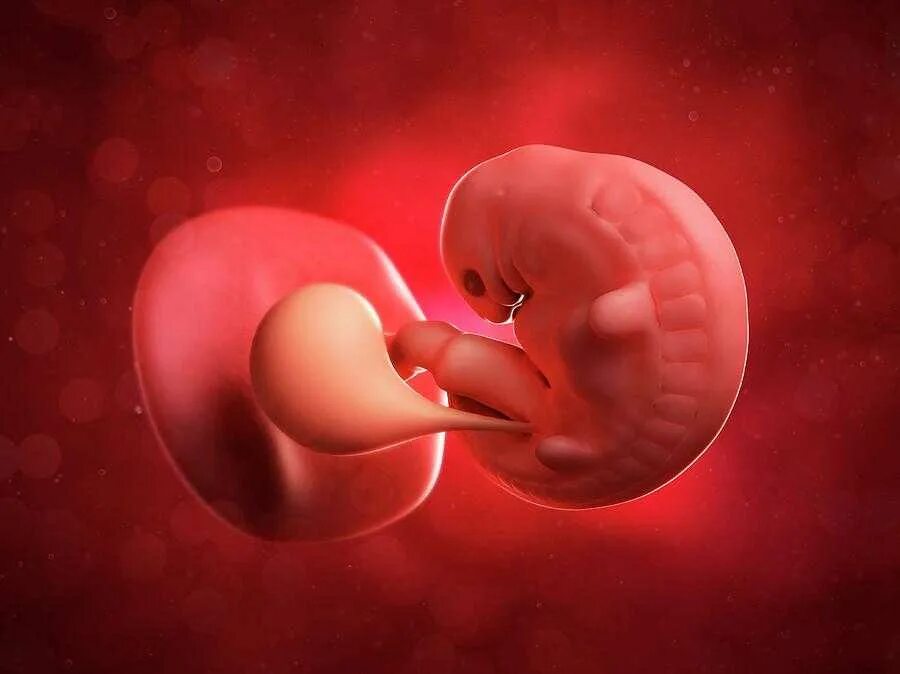

1 9 неделя беременности